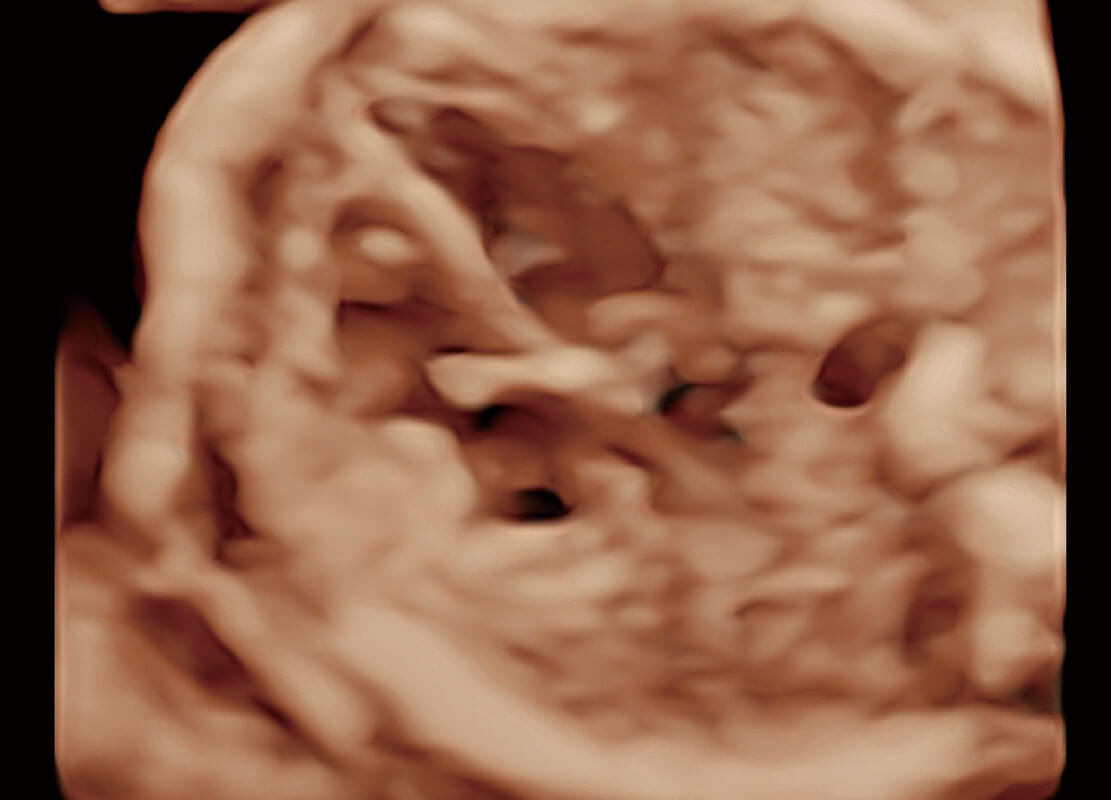

P60搭载一系列胎儿心脏成像技术,实现精细的胎儿心脏评估。

四腔切面

胎心容积成像